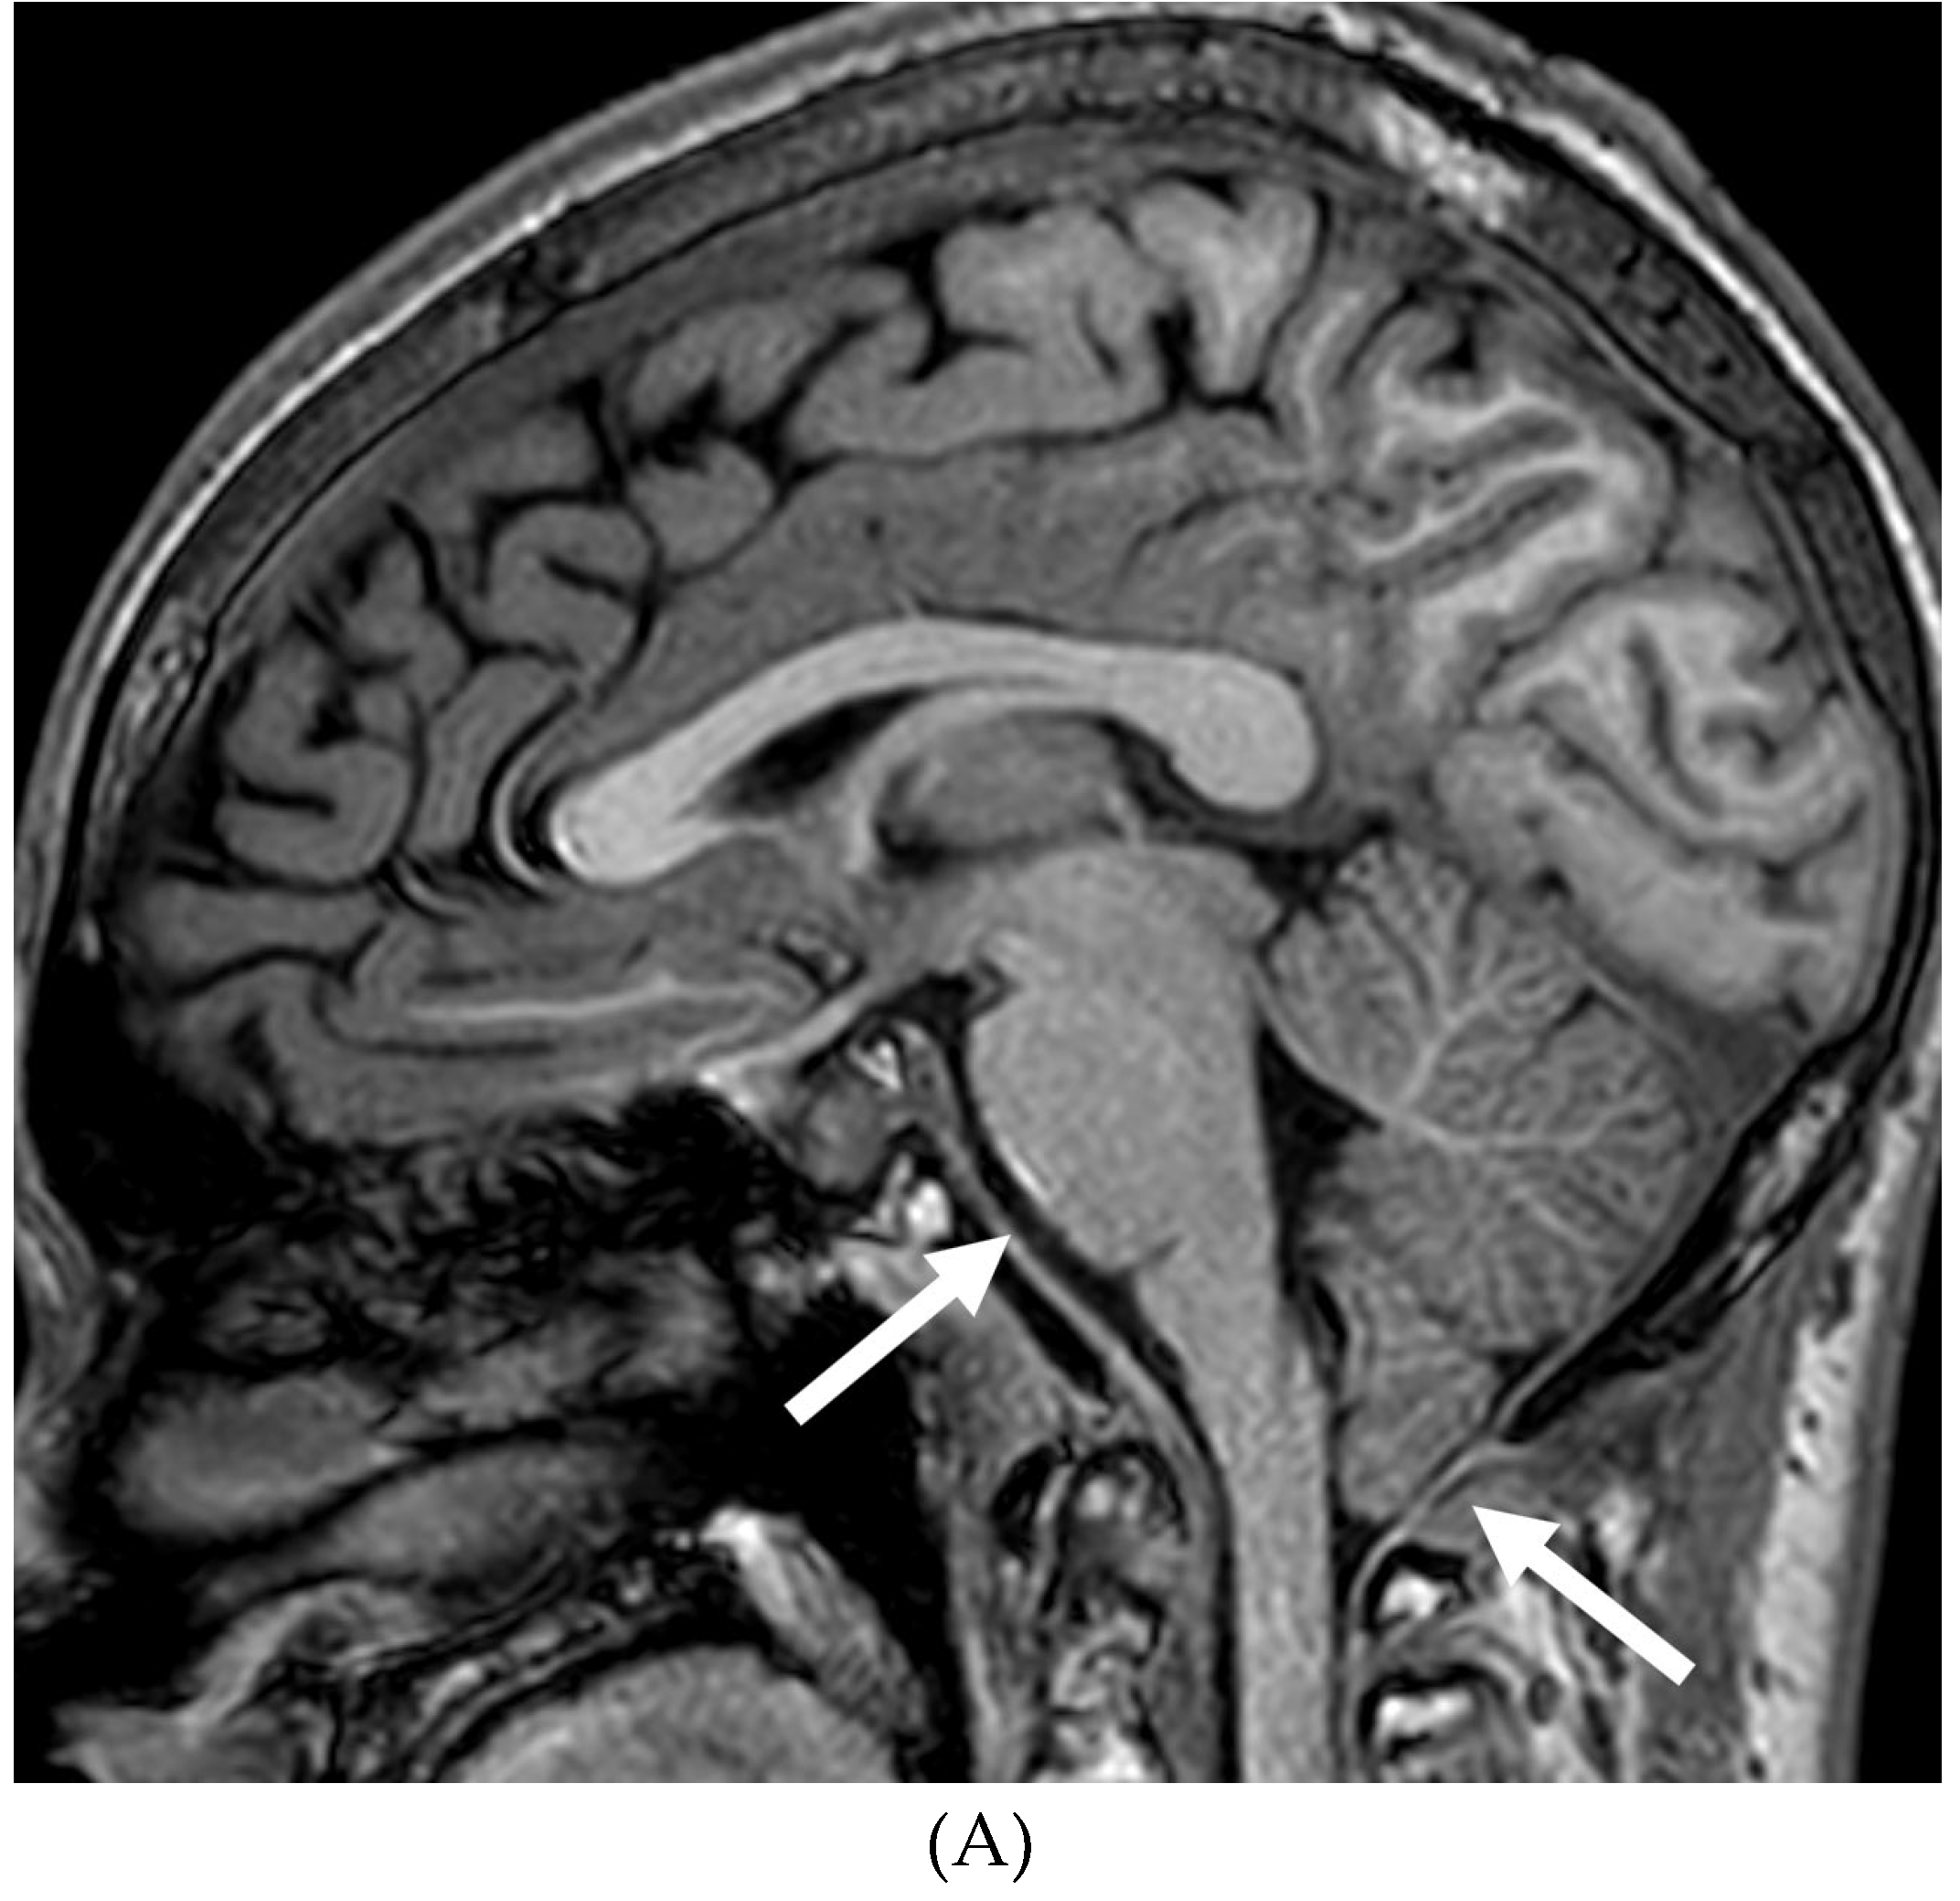

INTRACRANIAL HYPOTENSION (IH)

- Peterson EE, Riley BL, Windsor RB. Pediatric Intracranial Hypotension and Post-Dural Puncture Headache. Semin Pediatr Neurol. 2021 Dec;40:100927. Epub 2021 Sep 3. PMID: 34749914. [CrossRef]

- Schievink WI, Maya MM, Louy C, Moser FG, Sloninsky L. Spontaneous intracranial hypotension in childhood and adolescence. J Pediatr. 2013 Aug;163(2):504-10. Epub 2013 Feb 28. PMID: 23453548. [CrossRef]

- Shah LM, McLean LA, Heilbrun ME, Salzman KL. Intracranial hypotension: improved MRI detection with diagnostic intracranial angles. AJR Am J Roentgenol. 2013 Feb;200(2):400-7. PMID: 23345364. [CrossRef]

- Yuh EL, Dillon WP. Intracranial hypotension and intracranial hypertension. Neuroimaging Clin N Am. 2010 Nov;20(4):597-617. PMID: 20974378. [CrossRef]

- Medina JH, Abrams K, Falcone S, Bhatia RG. Spinal imaging findings in spontaneous intracranial hypotension. AJR Am J Roentgenol. 2010 Aug;195(2):459-64. PMID: 20651205. [CrossRef]